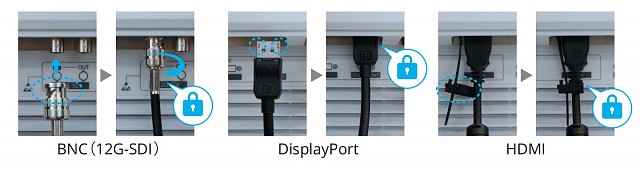

- DisplayPort 1.2、12G-SDI和HDMI,可轻松连接

- 12G-SDI(BNC)用于长距离连接

使用附带的电缆盖,可以将电缆整齐地存放在视线之外,从而提高手术室的安全性和卫生性。